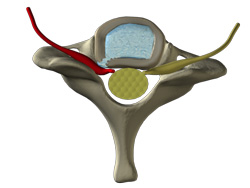

The non-contained disc may cause neck but usually pain into the extremities (one or both arms). This disc condition causes you pain because its nucleus pulposus (the center of the disc) has escaped through tears in the anulus fibrosus (the outer layers of the disc) and found itself in the spinal canal where it isn’t supposed to be. The anulus fibrosus no longer contains the nucleus pulposus.

The non-contained disc irritates the spinal nerves with a chemical reaction or with pressure. Normally, the nucleus pulposus' fluid has never been in the spinal canal, and when it does enter, it causes a chemical reaction around the nerve to cause pain. The nucleus pulposus' fluid chemically irritates the spinal nerves just by its mere presence in the canal, and, if enough of it escapes into the canal, its mass presses on spinal nerves causing pain into the arm.